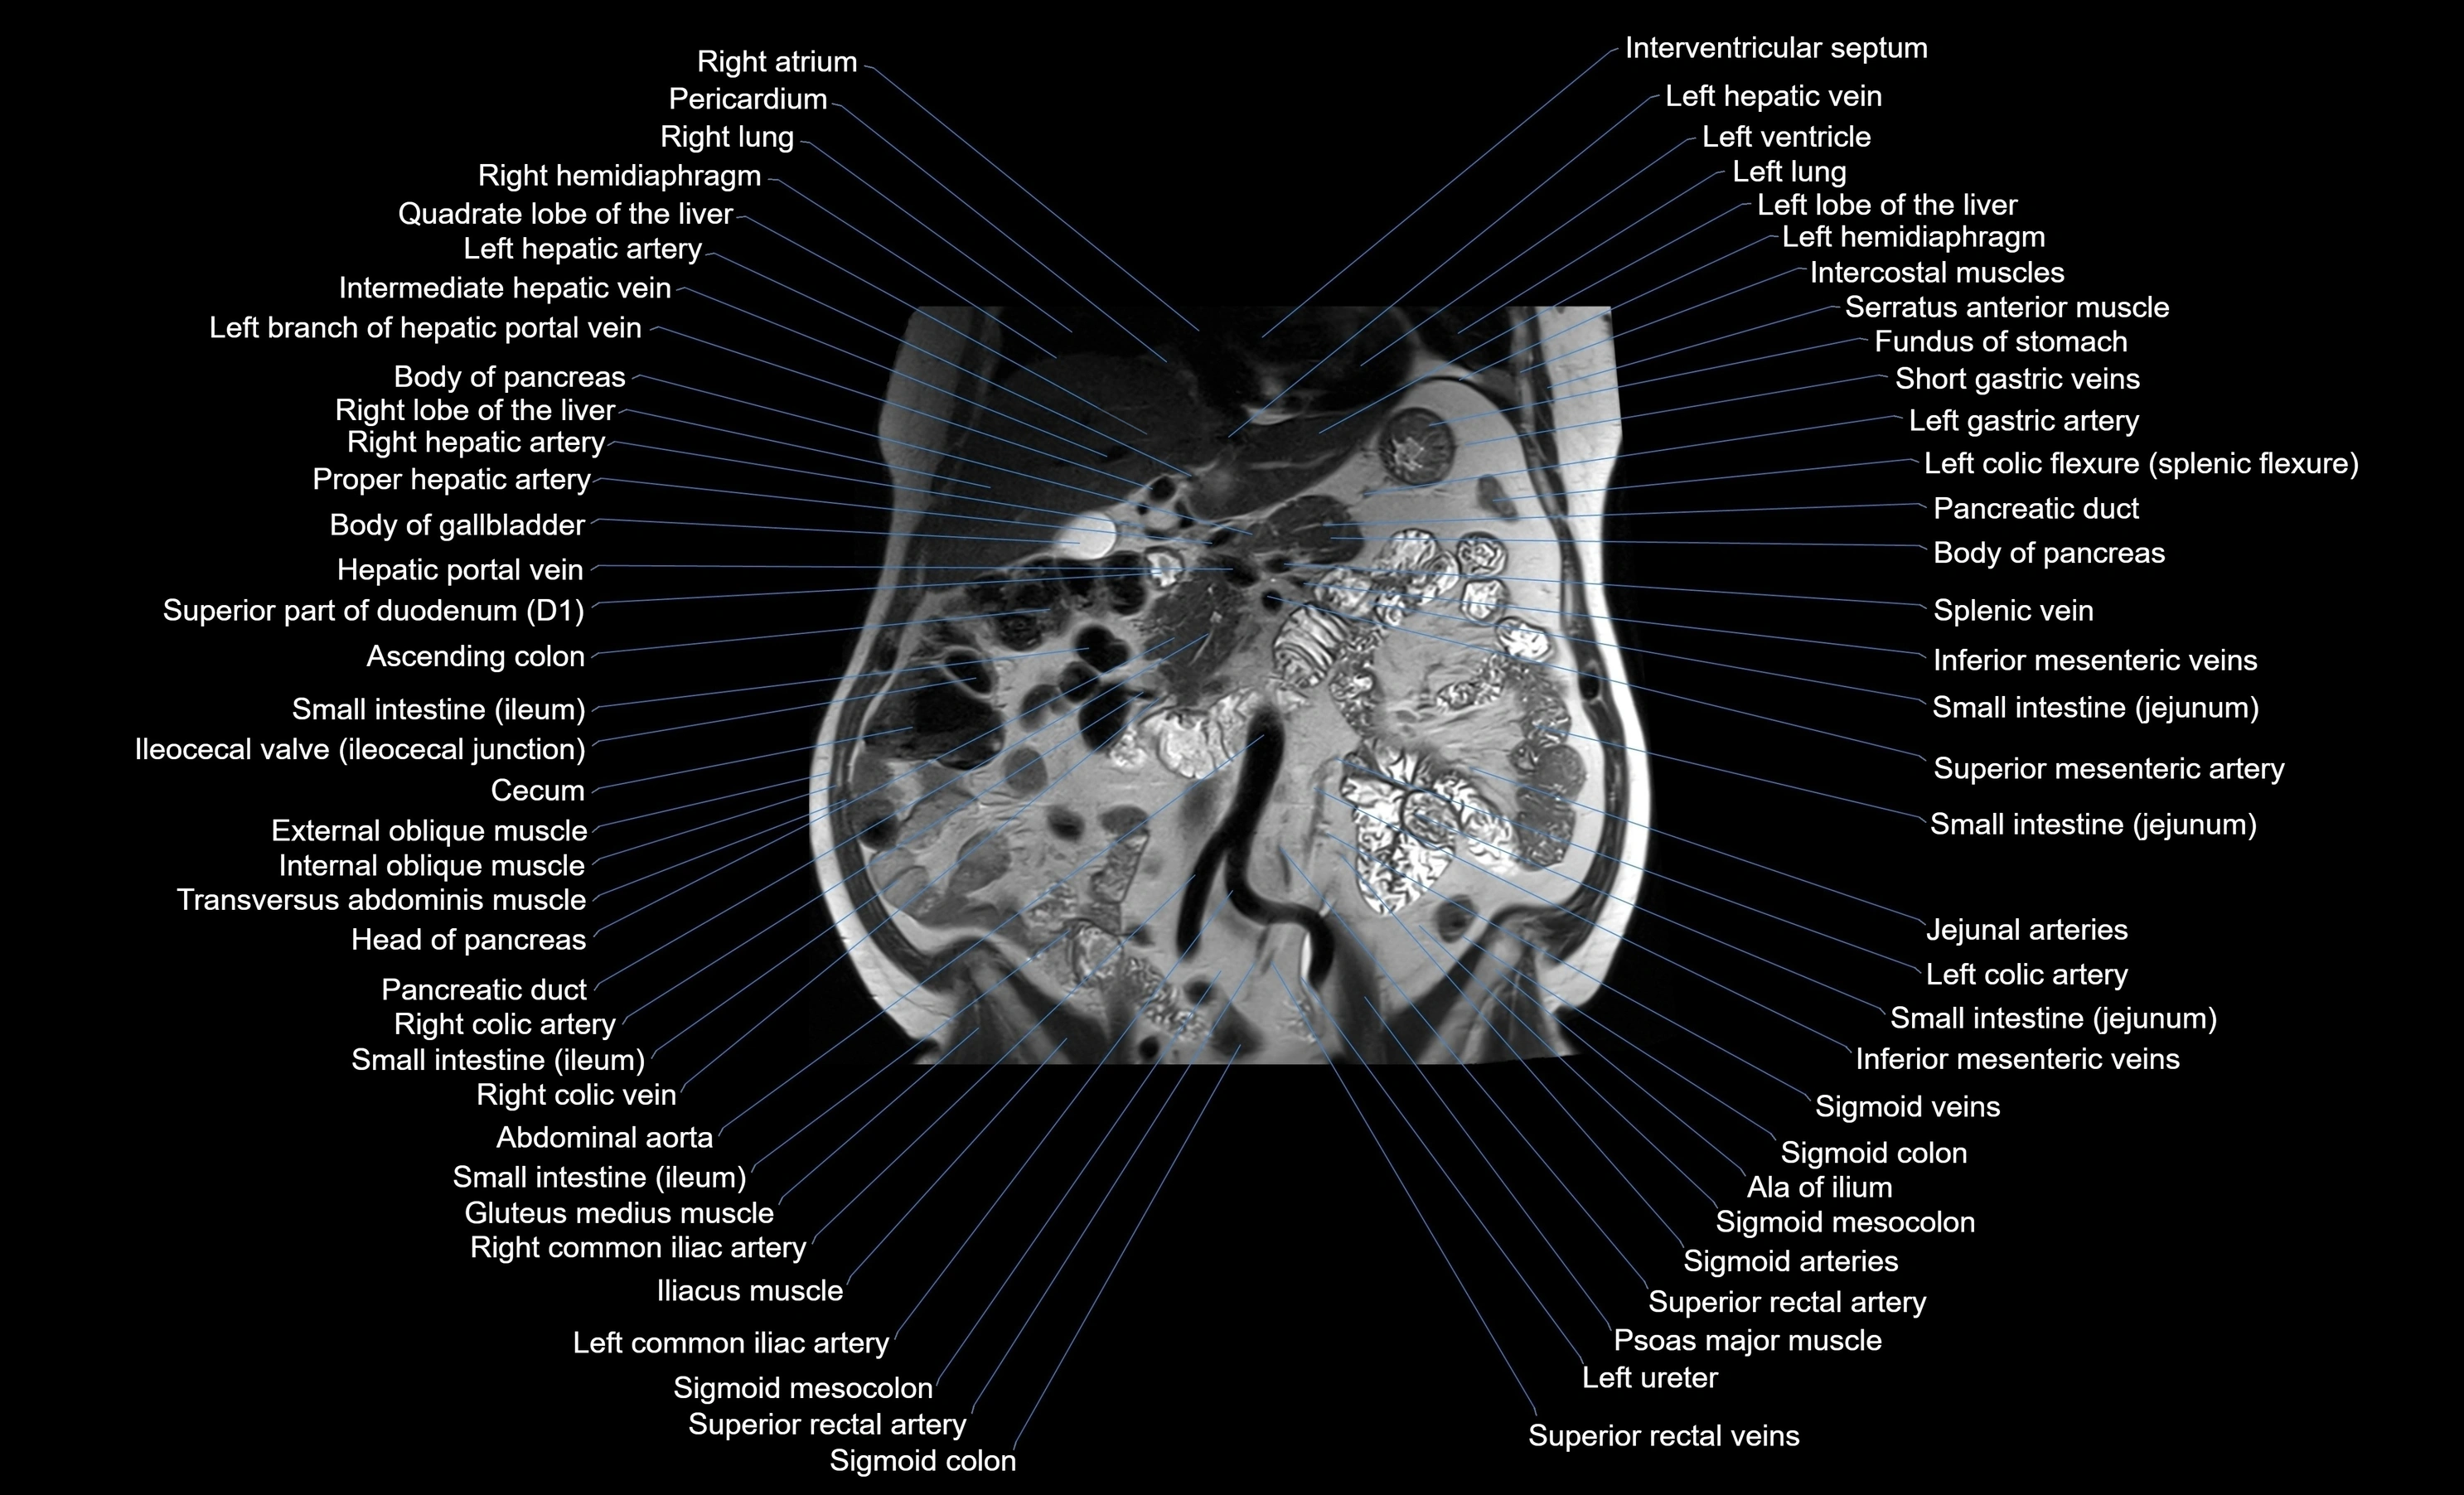

MRI images